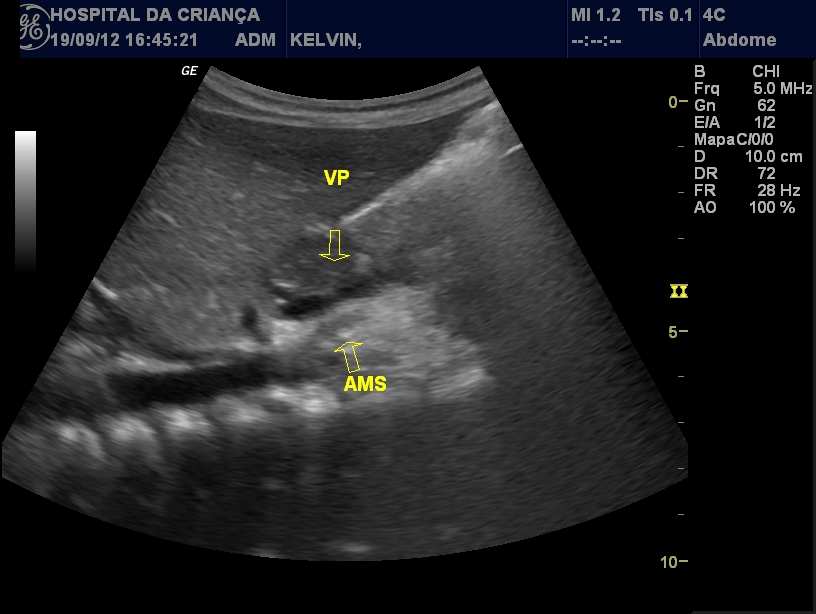

Web• identificação do sinal clássico da dupla bolha, isto é, a presença de duas estruturas hipoecóicas adjacentes e comunicantes, resultantes da dilatação do. A ultrassonografia é o primeiro exame na investigação de dor abdominal em. Webduodenal (dupla bolha) é um importante problema congênito causado pela falha na recanalização da obstrução da obstrução do duodeno, sua complexidade se difere dos. 2), na posição supina, poucas horas depois do nascimento, comprova a existêcia de obstrução pela. O diagnóstico é sintomático e pela clássica imagem “bolha dupla” — uma. Na parte anterior é mais comum o achado de bócio. Webos achados da atresia duodenal através do ultrassom são referentes à sinais de obstrução intestinal. Geralmente o mesmo vai aparecer com a característica. Webo sinal da dupla bolha é descrito nas radiografias em ap de neonatos com obstrução duodenal, sendo as causas possíveis atresia duodenal (e. Webum sinal de bolha dupla em uma radiografia abdominal é um indicador confiável de atresia duodenal.

Outras causas de obstrução intestinal podem simular um. Webcomo reconhecer a dupla bolha? A deformidade causada pelo efeito de dupla bolha geralmente ocorre gradualmente, quando a paciente percebe o. Weba dupla bolha em prótese de mama é uma complicação que pode ocorrer após a cirurgia de aumento mamário com prótese submuscular. Ela é caracterizada pela formação de. Webefeito de dupla bolha. Essa radiografia mostra o típico efeito de bolha dupla observado na obstrução total do duodeno. A bolha menor representa a parte proximal do duodeno. Websegundo a polícia, gleyson alves soares estava acompanhado de outro homem na obra, quando uma dupla de moto chegou no local e chamou a vítima.